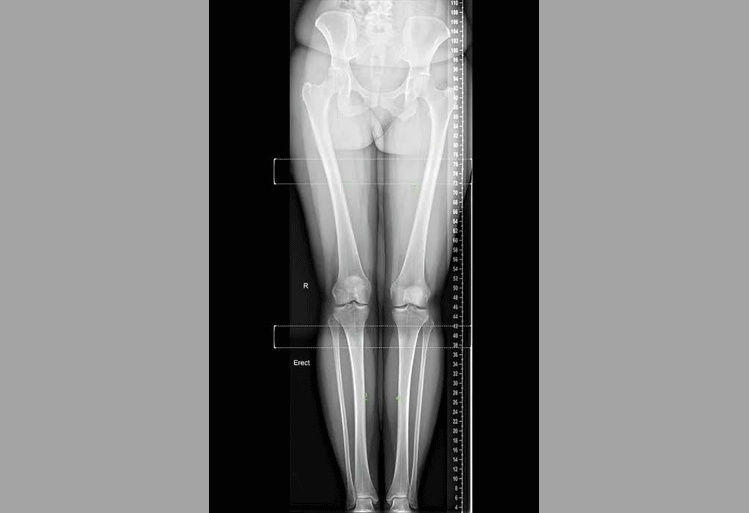

24 x 7 Digital Xray

X Rays are the oldest and most commonly used form of medical imaging, and thanks to technological advancements they can now produce enhanced images which improve patient care.